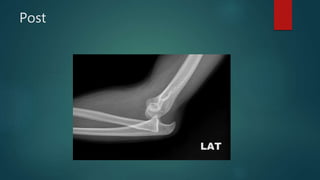

Radiographs are performed to ensure a congruous reduction has been

achieved and to evaluate for the presence of fractures not visualized on the

prereduction radiographs